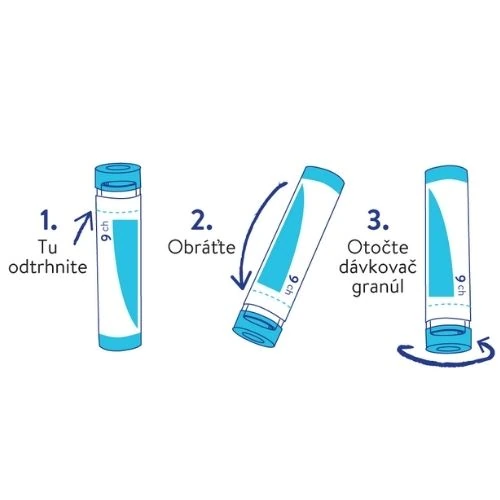

Homeopatický liek užívajte podľa pokynov lekára alebo lekárnika, prípadne takto:

Dávkovanie: 5 granúl 2 až 5-krát denne

Spôsob použitia: granuly môžete nechať rozpustiť v ústach alebo ich rozmiešať v malom množstve vody, ktorú následne vypijete. S nástupom úľavy sa interval podávania postupne predlžuje.